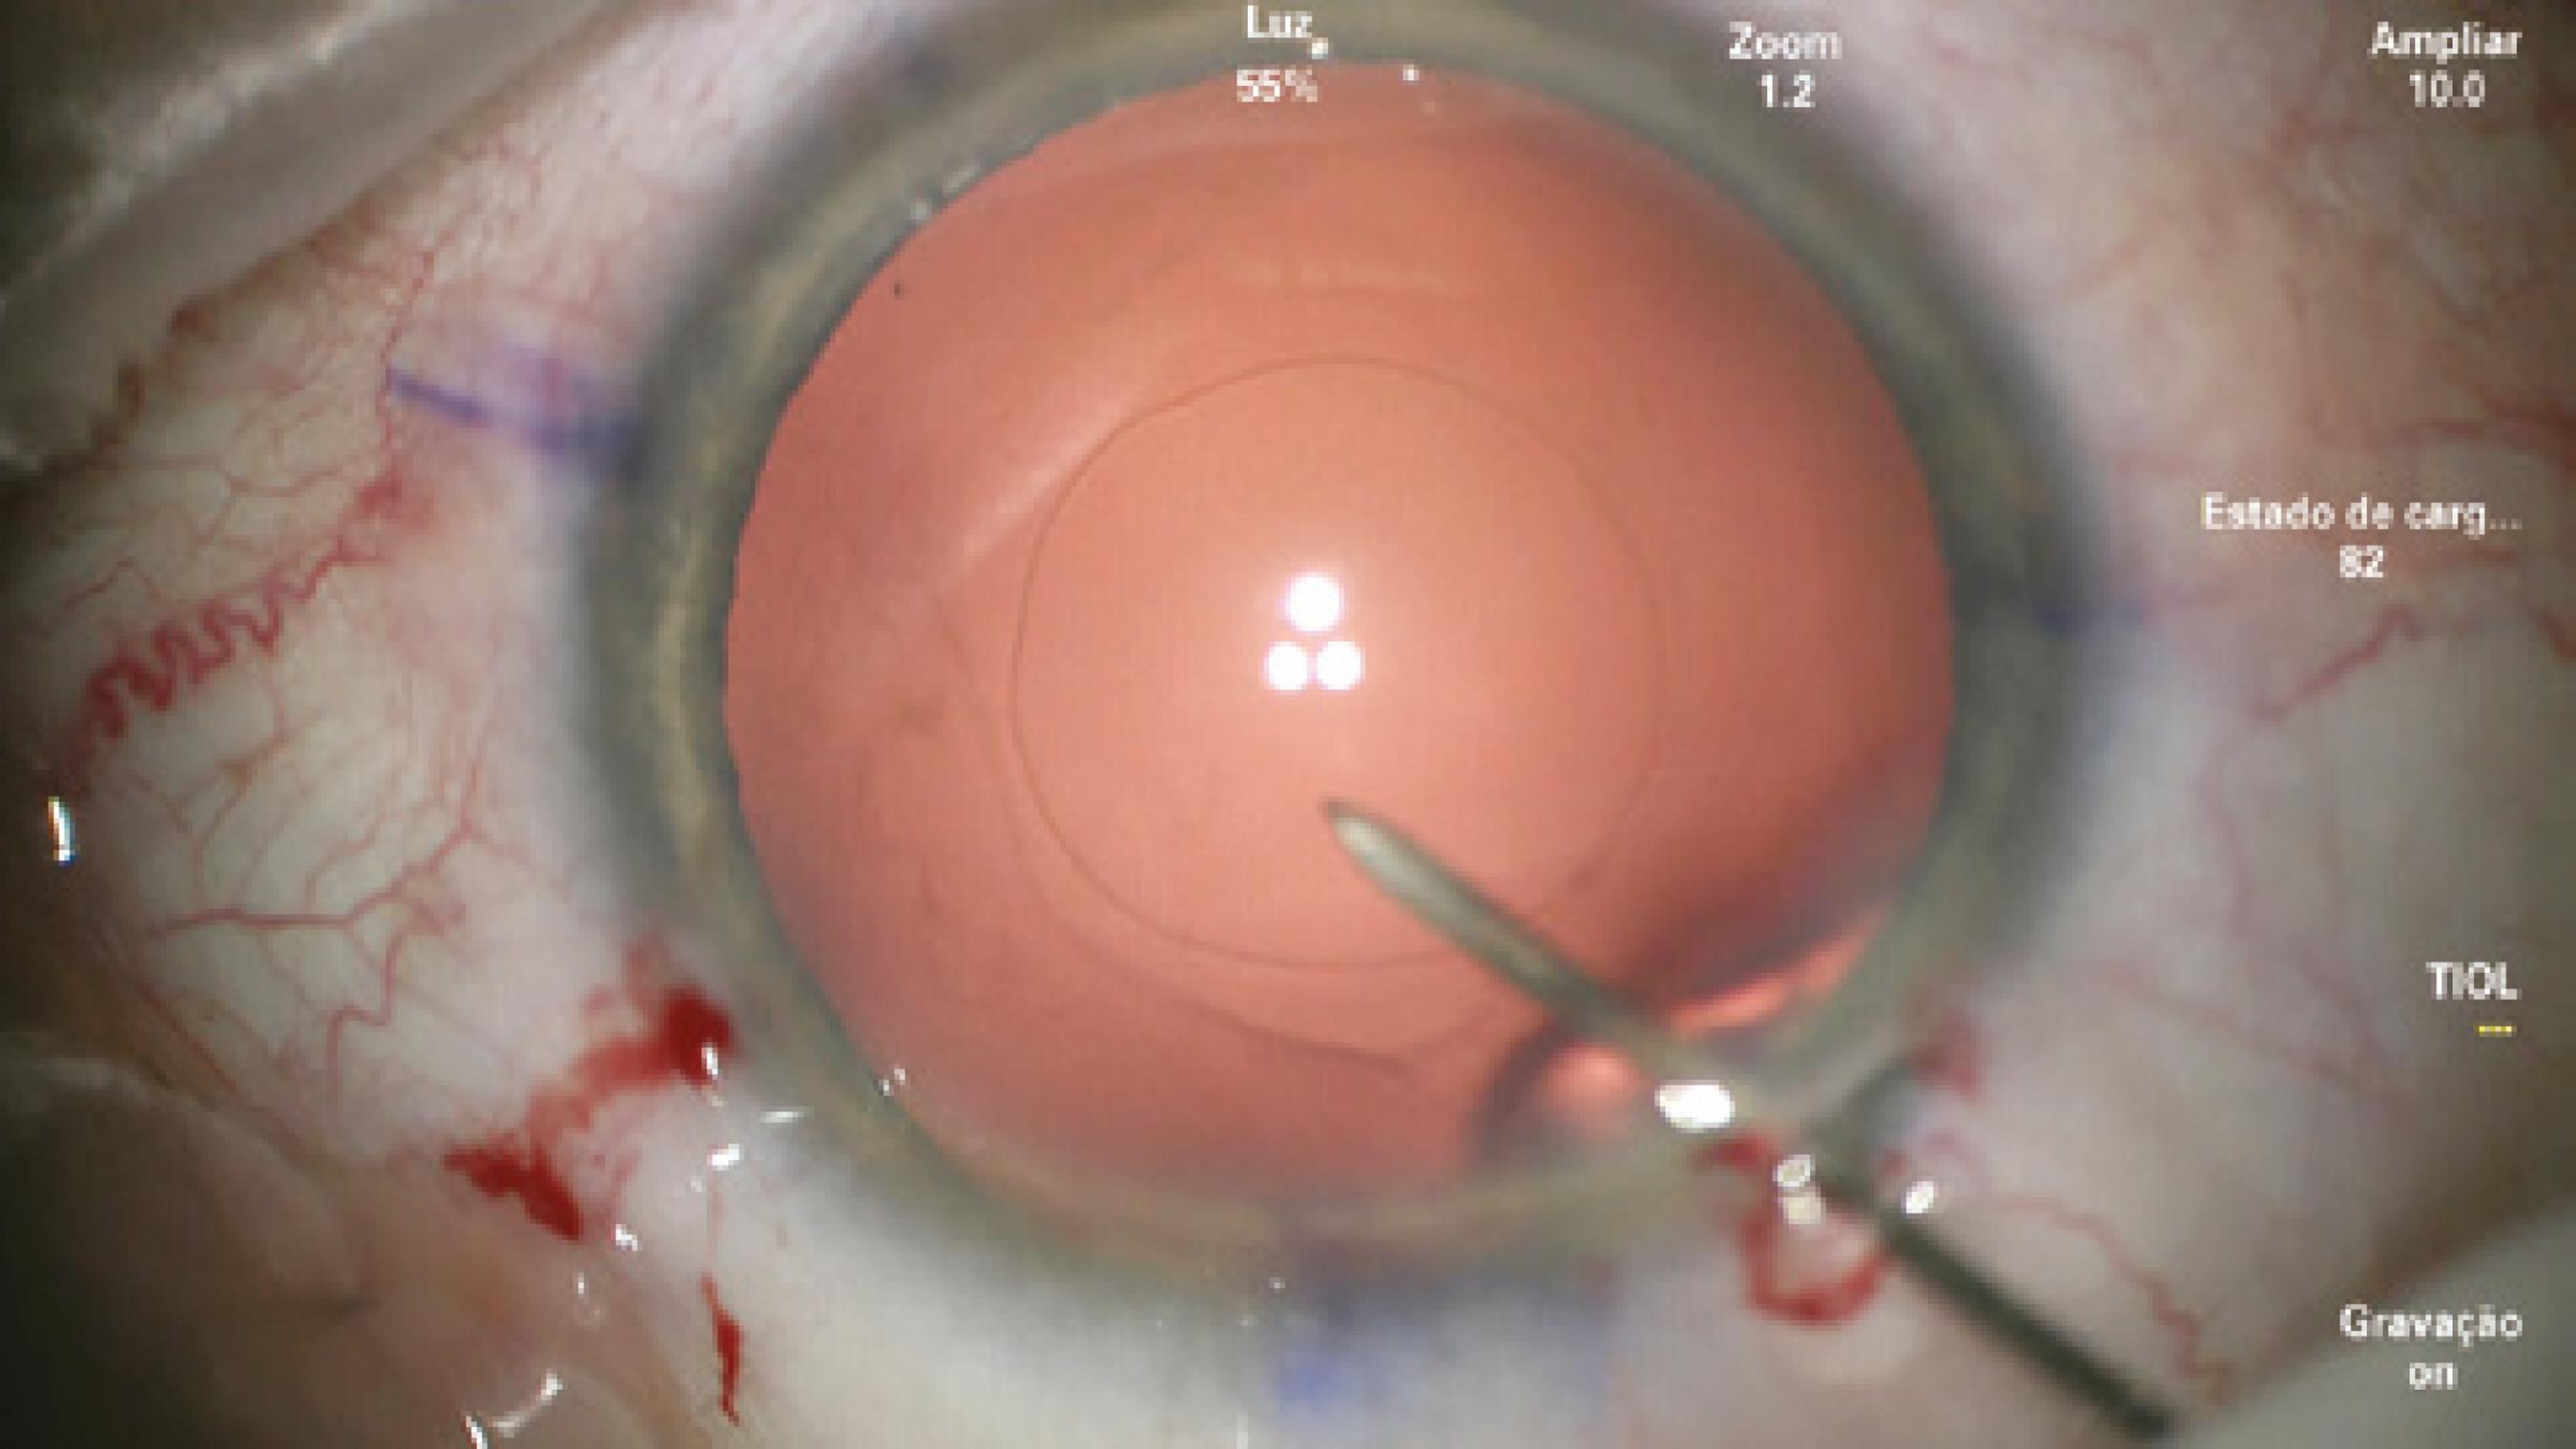

After confirming the 14-mm W-W diameter with calipers, phacoemulsification and cortical aspiration were performed without complications. To perform PCCC, the capsular bag was filled with a cohesive viscoelastic device (ProVisc®; Alcon Laboratories, Inc., Fort Worth, TX, USA). A 27-gauge needle mounted in a dispersive ophthalmic viscosurgical device (OVD; Viscoat®, Alcon Laboratories, Inc.) was used to perform the initial puncture of the central posterior capsule and inject dispersive viscoelastic into Berger's space to avoid rupture of the anterior hyaloid membrane (Figure 1). However, as soon as the posterior capsule was punctured, a tear extended spontaneously to the periphery in a similar fashion to an Argentinean-flag sign in the anterior capsule (Figure 2). Because the eye was well pressurized with a stable anterior chamber, the anterior hyaloid membrane remained intact and no vitreous humor prolapsed. IOL insertion into the capsular bag was performed using a bimanual technique with extreme caution to avoid extending the tear, vitreous humor prolapse, and dropping the IOL into the vitreous cavity.